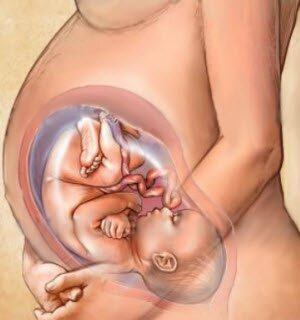

29 неделя беременности: сколько это месяцев и чего ожидать?